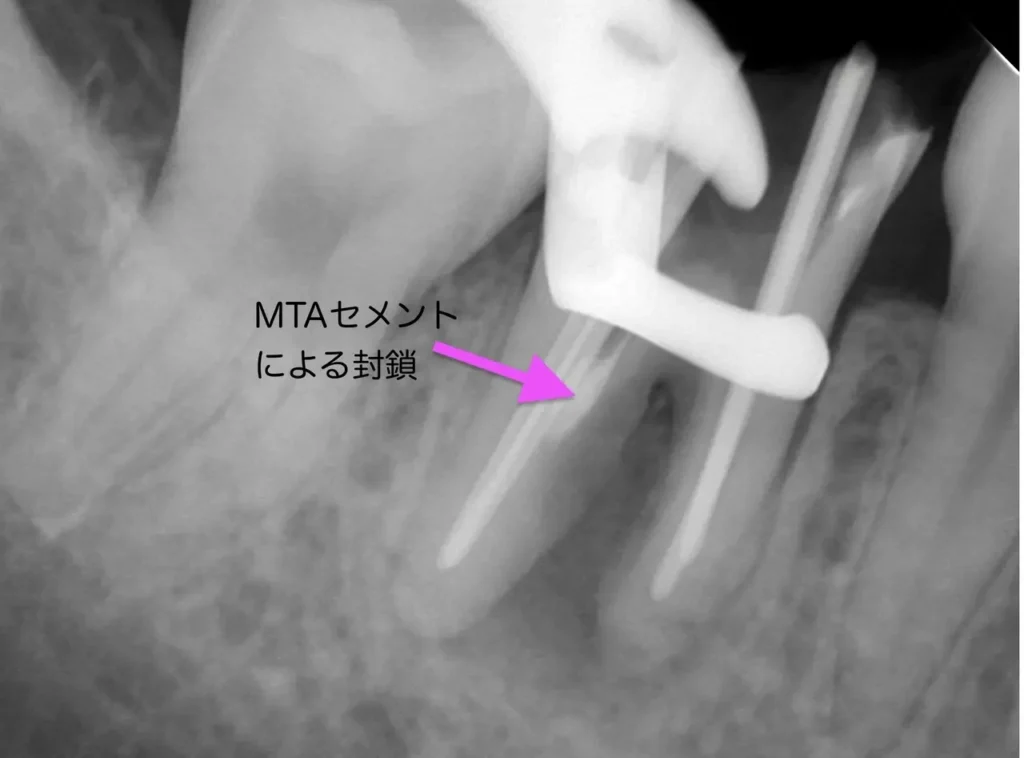

術中(ポイント試適)

レントゲン写真

孔はMTAセメントで封鎖しました

術後レントゲン写真

根管充填もMTAセメントによる穿孔封鎖もうまくいきました